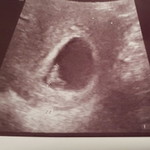

Read moreIf u dont wanna waste money, u can go 8 weeks. Cos ard 6 to 8 weeks, u can see the heartbeat. However, if u are anxious and need someone to confirm ur pregnancy. Or if u have some worries like u see spotting, then u can go early. But can only see the waterbag. At this period, pls take folic acid 5mg everday.

I went to gynae after testing positive to double confirm with ultrasound.